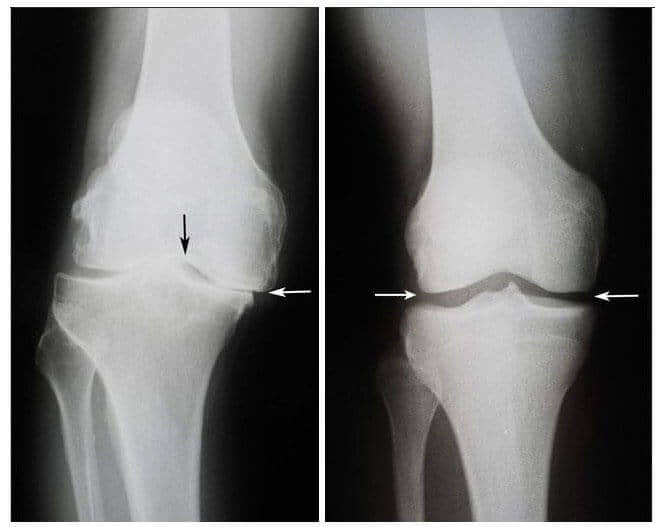

Onda se dogodilo čudo. Ovaj doktor je počeo svaki dan dolaziti kod Jovane i mazao je ovom ljekovitom mašću. Nekoliko sedmica kasnije, uspjela je da ustane iz kolica i da sama ode kod doktora. Nakon šest sedmica, zglobovi Jovane Bulatović su se potpuno oporavili od osteoartritisa. Snimci su to pokazali.

S lijeve strane: Snimak zgloba koljena Jovane Bulatović, 75. Hrskavično tkivo je potpuno uništeno. Preporuka doktora je da se uradi operacija koljena i da se zglob zamjeni vještačkim.

S desne strane: Snimak zgloba desnog koljena Jovane Bulatović nakon liječenja gelom Bone Control.